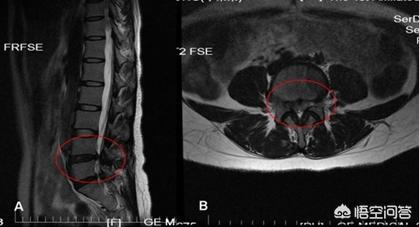

腰腿痛在做腰椎间盘CT检查的时候,往往有的人会发现有钙化,这个钙化可以是后纵韧带钙化,也可以是突出的髓核钙化,有的人钙化点压迫刺激到神经造成症状,相较于没钙化的处理要麻烦!

钙化,实际上是突出物较久或者长期腰痛,髓核脱水变性,慢慢形成的,临床上,我问的时候,多数是超过3~5年之上的人才会出现这种钙化,也许没有症状,可是早就已经发生椎间盘突出。

的确不少人在突出物钙化之后,康复难度会增加,不过这未必和钙化本身有关系,多数的钙化不会发生在突出物和神经根接触的地方,即便有也可以保守处理看一下,钙化的同时也表示问题发生的很早,持续很久,难度大一点是正常的。